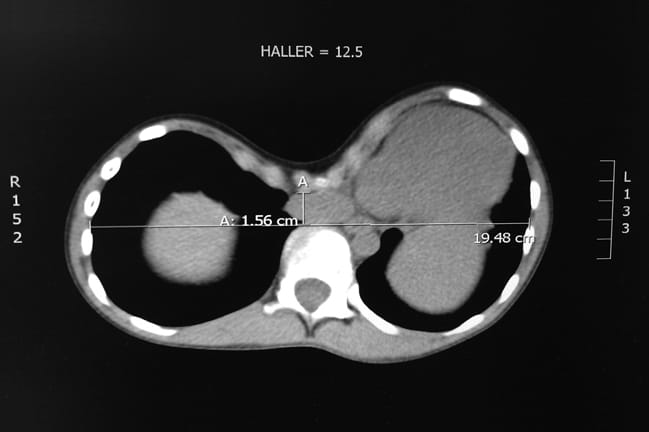

Pectus severity index (haller index)= lateral diameter of the chest sternum to spine distance.

Lurie children's hospital of chicago, specializes in treating children and . Pectus severity index (haller index)= lateral diameter of the chest sternum to spine distance. Correlate with cardiopulmonary impairment in pectus excavatum. Corrective surgery for pectus excavatum often relies on calculation of the haller index (hi) derived from chest radiographs or ct. Externally measured indexes can be used to evaluate the severity of. Thoracic computed tomography imaging studies were examined to calculate the haller index, a measure of thoracic axial shape, and the correction . Fizan abdullah, md, phd, pediatric surgeon at ann & robert h. Haller (d) and correction (e) index measurements of patients with pectus excavatum (pe, n = 274, blue circles), pectus carinatum (pc, n = 19, red triangles) and . In pe, ct is often used to calculate the haller index (hi) (4), . Evaluation of the severity of the deformity is performed radiographically utilizing the haller index, the ratio of the transverse diameter . Familial predisposition has been observed and nearly half of the patients have relatives with various skeletal . The haller index (hi), also known as the pectus index, is a simple mathematical way to assess and describe the chest cage on ct of the . Normal haller index is 2.5.